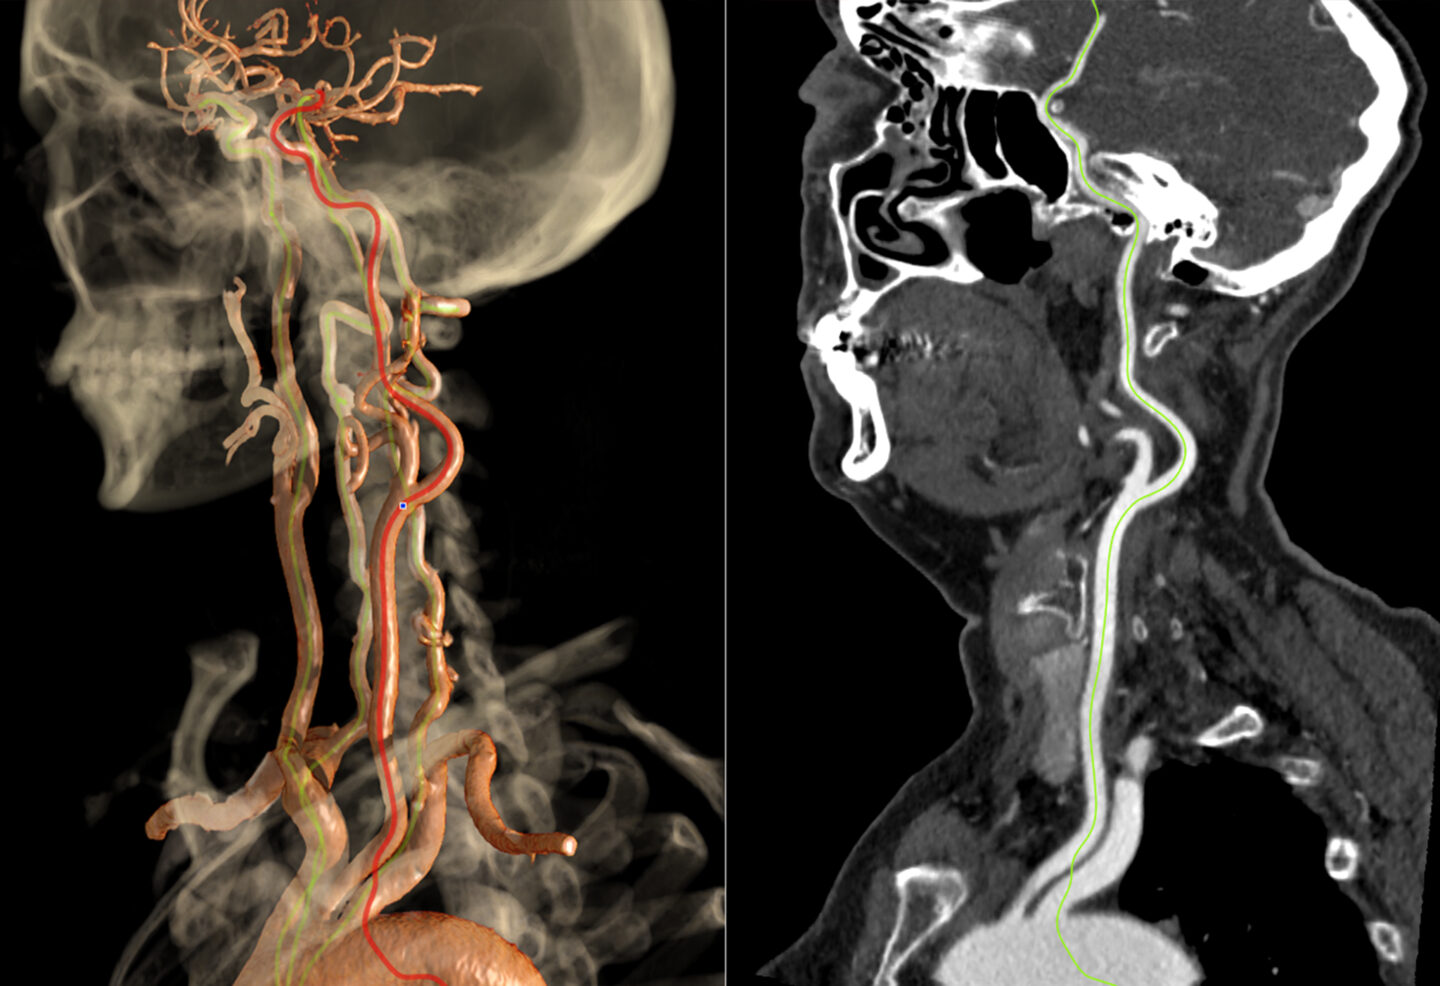

Enhance Your Carotid Imaging Efficiency

Learn how a major health system implemented Vitrea’s CT Carotid Auto Vessel application and saved nearly 3 minutes per study.